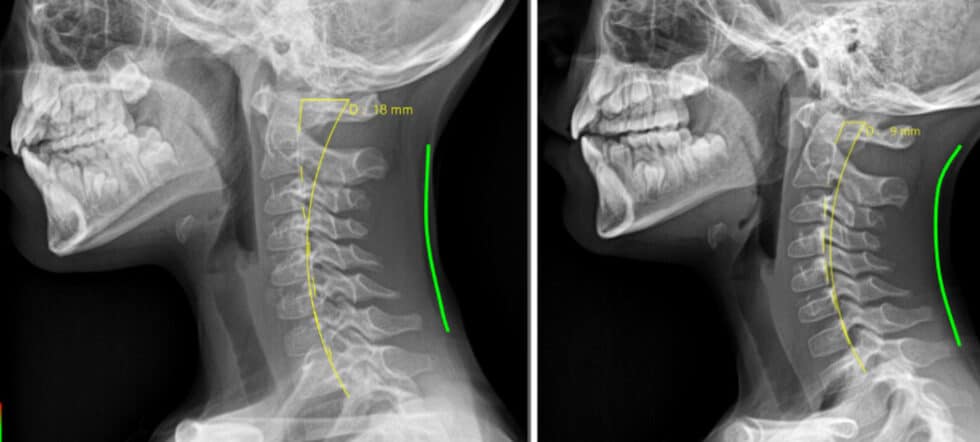

These images are of a child who presented with toe walking that was not resolving with typical bodywork protocols. His provider recognized a tongue tie and sent him here for tongue tie release with oral myofunctional therapy. These photos are 3 months apart. During that window, we treated the child with 2 months of oral myofunctional therapy and a functional tongue tie release with our Lightscalpel CO2 laser. The second image was just a few days after the tongue tie release procedure, where the patient not only showed resolution of toe walking, but also showed a return to healthy curvature of the cervical vertebrae with release of head and neck tension. It is important to state that success is dependent on a collaborative team approach that addresses not only the restriction of the tongue tie, but also addresses the compromised oral function and the surrounding muscle and fascial (myofascial) tension that is associated with it.